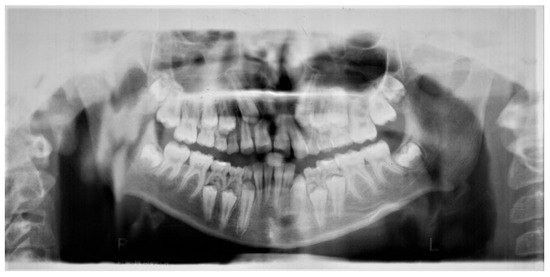

2. Case Report